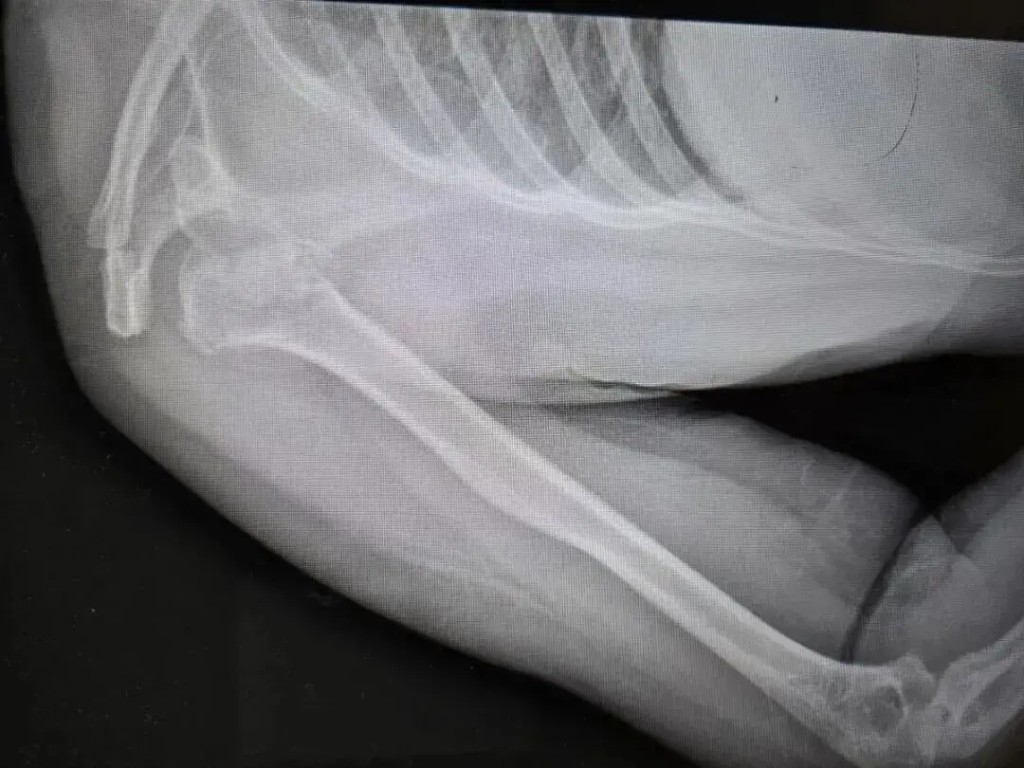

張大姐因不知患有癲癇症,睡夢中病發「震」斷自己手臂骨成七、八截。大河報

張大姐送醫後被發現右上臂粉碎性骨折,需轉送河南省人民醫院創傷骨科才能駁回。

據河南省人民醫院創傷骨科主任劉濤指,張大姐右肱骨近端四部分粉碎性骨折,且伴有罕見的肱骨頭後脫位,肩膀骨碎成七、八塊,「高空墜落、車禍撞擊才會有這麼大的力」。